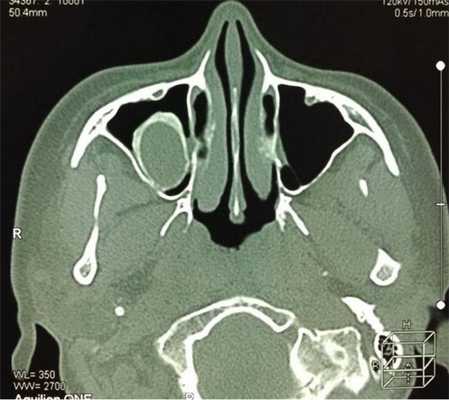

Тотальное заполнение жидкостью (кровью?) левой верхнечелюстной пазухи, повреждение носовой перегородки на компьютерной томограмме